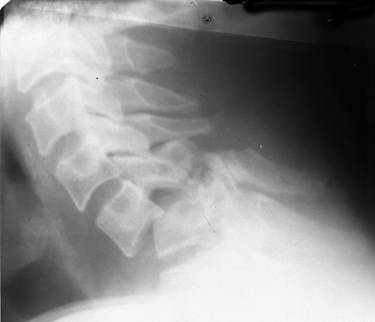

Fig.92 – Bloc vertebral cervical congenital 414e46e |